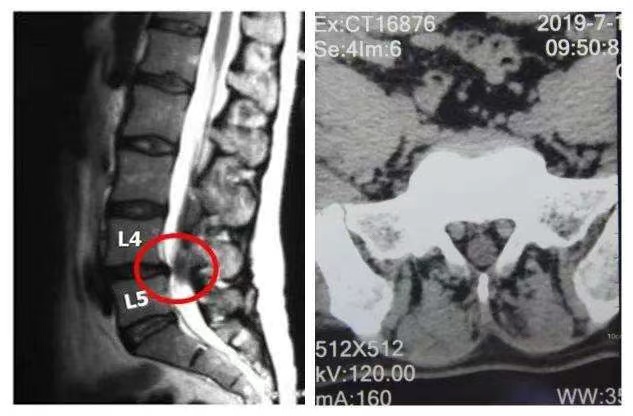

如果我们是经常闪腰,那就要注意是不是腰椎间盘突出引起的了。

1.尽量卧床休息 首先要保持舒适的姿势,安静休息。减少肌肉筋膜组织的受力,使疼痛缓解。对于疼痛严重者应该延长卧床时间。轻微的闪腰,只要休息个1-2天均可以自动痊愈。对于疼痛严重者应该延长卧床时间。但若疼痛持续或愈来愈痛,则需尽早就医。需要排除是否存在椎间盘突出或脱出,有没有腰椎不稳或滑脱等情况。